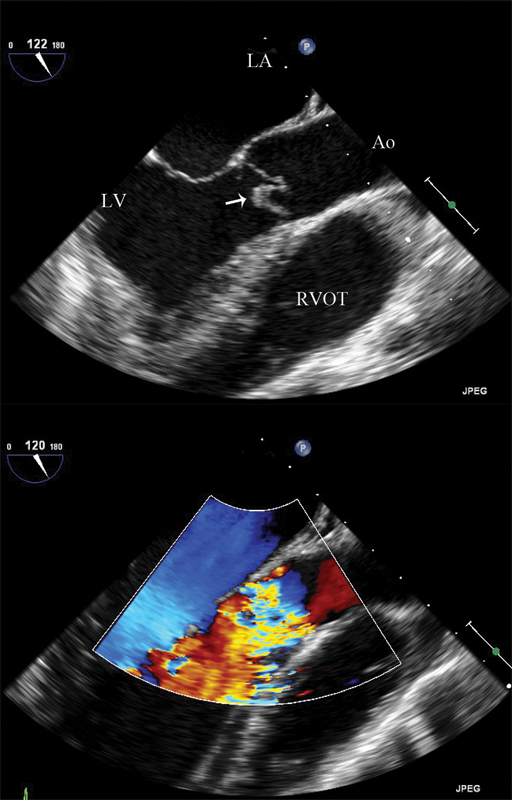

فحوصات تشخيصية لبعض امراض القلب والشرايين التاجية